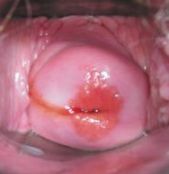

Народное лечение эрозии шейки матки и трещин сосков маслом шиповника. |

Народное средство лечения эрозии шейки матки, трещин сосков и ссадин – масло шиповника.

При эрозии шейки матки вагинально применяйте обильно смоченные маслом тампоны.

Часть 10 - Лечение эрозии шейки матки